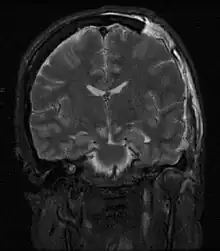

| Severely high ICP can cause the brain to herniate. | |

Severely raised ICP, if caused by a unilateral space-occupying lesion (e.g. a hematoma) can result in midline shift, a dangerous sequela in which the brain moves toward one side as the result of massive swelling in a cerebral hemisphere. Midline shift can compress the ventricles and lead to hydrocephalus.[16]